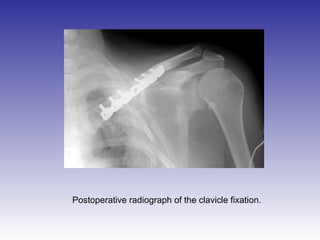

Postoperative radiograph of the clavicle fixation.

Postoperative radiograph ofthe clavicle fixation.